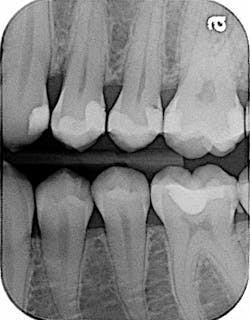

Patients get angry over poor contacts and food traps. They don’t want to be bothered with the hassle of food impaction, and they may not even know that poor contacts are a source for further decay or even periodontal effects. So, it’s important that we get contacts right the first time. After all, it’s not that hard to check for open contacts at the end of treatment. This point of aggravation comes up in my office more times than I would like to think, which is why I want to review the importance of getting good contacts when we restore teeth, particularly when we complete fillings for patients.

Further, there usually is not much I can do to adapt in these situations, but contacts are different. I have only found a couple of ways to make a really good contact, especially when restoring cavities with composite restorations. I will skip amalgam fillings, because condensing amalgam tightly is not typically a problem; it’s usually the composite fillings that create problems for us.

Before ring systems came into use, traditional Tofflemire band holders and bands were used. I find the bands somewhat difficult to use, but you can make a contact if you use a softer, thinner band and some lateral condensing occurs on the band itself against the adjacent tooth. This precondensing and forming of the band helps ensure that a contact is formed.

I find the ring system design to be even more helpful. I have used the Garrison brand in the past, and I use Dentsply’s brand now. Both provide nice contours against the adjacent teeth; these contours help create optimal contacts. Sometimes, I still have to use a thin diamond or a 12-blade to shave off some of the interproximal overhangs to help guarantee that a smooth edge exists and a nice, popping contact sound occurs.